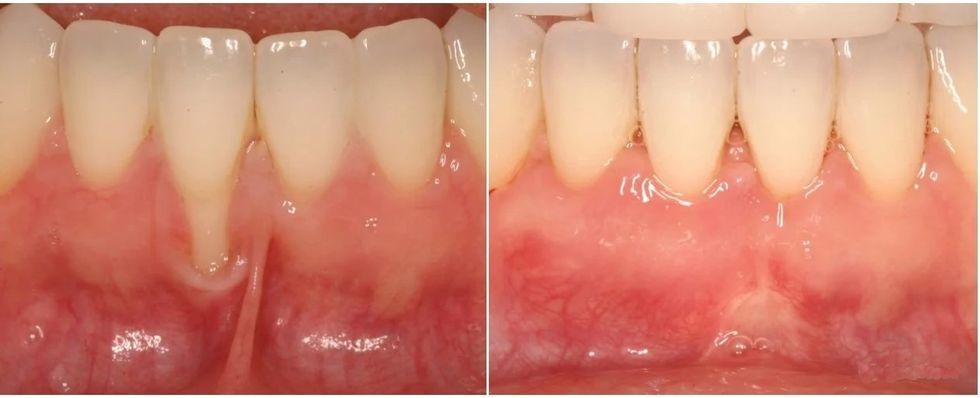

Graftimi i gingivës (mishrave të dhëmbëve) është një procedurë dentare për trajtimin e hollimit të mishrave të dhëmbëve ose recesionit (tërheqjes) së mishrave të dhëmbëve. Kjo procedurë zëvendëson indin e humbur rreth dhëmbëve tuaj dhe përmirëson shëndetin tuaj të përgjithshëm oral.

Graftimi i gingivës mbulon rrënjët e ekspozuara të dhëmbëve dhe i shton vëllim mishrave të dhëmbëve, duke përmirësuar shëndetin e përgjithshëm oral.

Rikonkstruksioni i recesioneve gingivale me grafte gingivale është një procedurë që ndihmon në rivendosjen e mishrave të dhëmbëve që janë tërhequr.

Ky intervenim mund të ndihmojë në mbrojtjen e dhëmbëve dhe të përmirësojë pamjen e buzëqeshjes suaj. /Telegrafi/